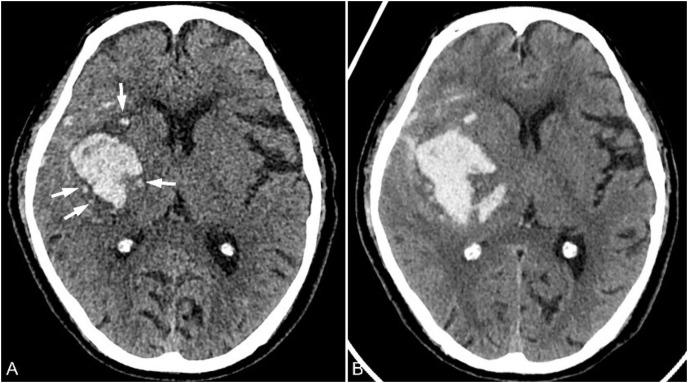

基于 CT 图像预测高血压性脑出血扩大的研究进展:综述。

Research advances in predicting the expansion of hypertensive intracerebral hemorrhage based on CT images: an overview.

Hematoma expansion (HE) is an important risk factor for death or poor prognosis in patients with hypertensive intracerebral hemorrhage (HICH). Accurately predicting the risk of HE in patients with HICH is of great clinical significance for timely intervention and improving patient prognosis. Many imaging signs reported in literatures showed the important clinical value for predicting HE. In recent years, the development of radiomics and artificial intelligence has provided new methods for HE prediction with high accuracy. Therefore, this article reviews the latest research progress in CT imaging, radiomics, and artificial intelligence of HE, in order to help identify high-risk patients for HE in clinical practice.

血肿扩大(HE)是高血压性脑出血(HICH)患者死亡或预后不良的重要危险因素。准确预测 HICH 患者发生 HE 的风险,对于及时干预和改善患者预后具有重要的临床意义。文献中报道的许多影像学征象均显示出对预测 HE 的重要临床价值。近年来,影像组学和人工智能的发展为 HE 预测提供了高精度的新方法。因此,本文综述了 HE 的 CT 影像学、影像组学和人工智能的最新研究进展,以期有助于在临床实践中识别出 HE 的高危患者。